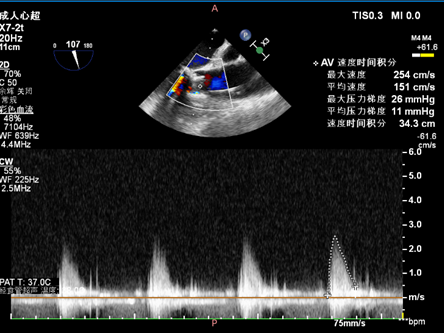

主瓣

术后

术前术后流速压差对比,术前最大速度464cm/s,平均速度316cm/s,最大压力梯度86mmHg,平均压力梯度46mmHg;术后最大速度254cm/s,平均速度151cm/s,最大压力梯度26mmHg,平均压力梯度11mmHg: